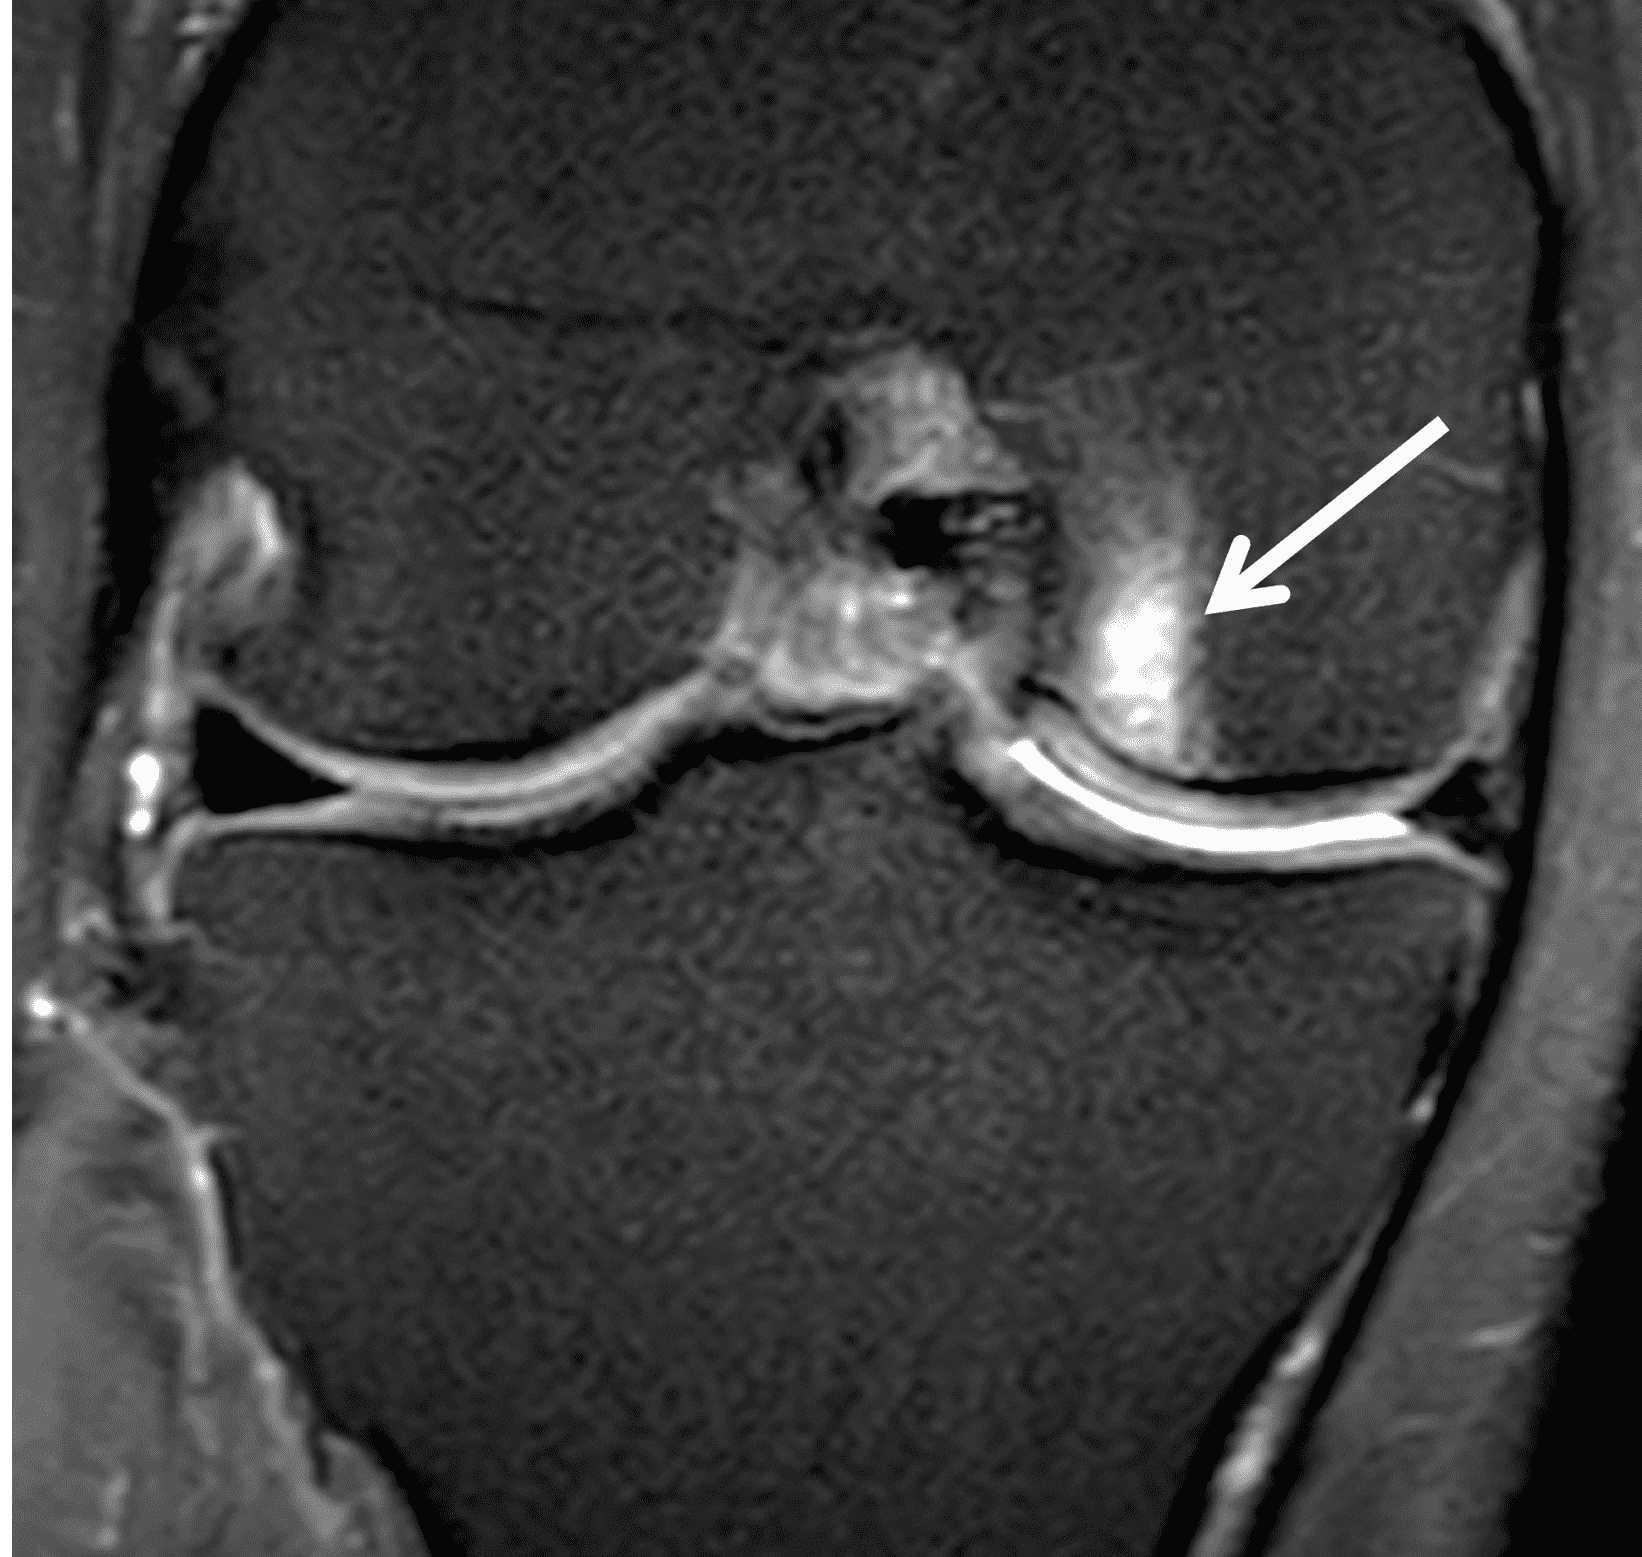

A 32-year-old man suffered a traumatic chondral injury to the medial femoral condyle that was treated with an osteochondral allograft 20 months previously. Representative images from a current knee MRI include (1A) coronal fat-suppressed fluid-sensitive and sagittal (1B) T1-weighted, (1C) proton density-weighted, and (1D) T2-weighted sequences. Are the post-operative MRI findings normal and expected, or abnormal and pathologic? Based on these images, would you characterize the procedure as a success or failure?

Figure 2: (2A) On the coronal image, the margins of the osteochondral graft are faintly visible (arrowheads). Both the graft and underlying bone show mild marrow edema, an expected finding. (2B) The T1-weighted image shows continuity of the marrow in the graft (asterisks) with the underlying bone, indicating osseous integration. A bioabsorbable pin (arrow) used for graft fixation is partly visible. (2C) The proton density-weighted image shows a low signal intensity seam (black arrow) between the native cartilage and transplant, as well as a defect in the subchondral bone plate of the graft (red arrow) where the pin was drilled, both normal findings. (2D) The T2-weighted image shows a smooth, congruent articular surface (arrows), restoring the normal anatomy, and a tiny subchondral cyst. No findings are present to suggest graft failure. The patient’s current symptoms were attributed to pathology elsewhere in the joint (not shown).

Successful osteochondral allograft procedure.

The postoperative imaging appearance of osteochondral allografts is similar to autografts (Figure 2).33 The subchondral bone plate of the donor and recipient sites do not have to match, but the articular surface should be congruent. Grafts that fail to incorporate by one year have a poor prognosis. Persistent marrow edema (beyond 12 months), a thick graft interface containing cysts or fluid, and subsidence of the graft are associated with poor osseous healing and worse outcomes. Extensive host marrow edema and severe synovitis may be a clue to immunologic rejection of the graft (Figure 18).21, 34